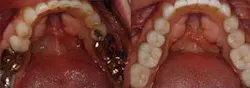

For patients to proceed with treatment in a comprehensive way, they must feel confident in our ability to deliver care. There are multiple methods of demonstrating capability to patients — clean and tidy offices, pleasant, long-term staff members, and patient testimonials. However, I have found that sharing photographs of restored arches that demonstrate the transformations possible with modern materials and techniques is very effective (Figs. 5 and 6; 7 and 8). Just as everyone appreciates how restorative dentistry can improve a person’s smile, patients also appreciate how posterior dentistry can improve a deteriorating situation — especially when the preoperative case reflects their own needs.